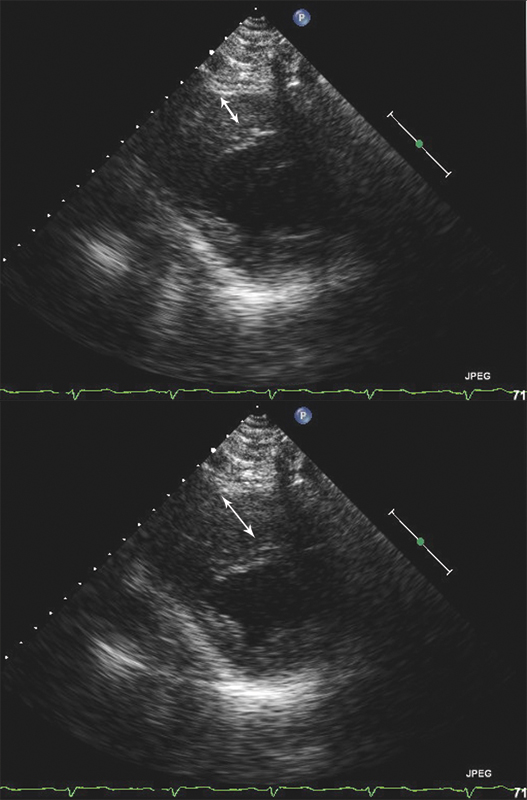

فحوصات تشخيصية لبعض امراض القلب والشرايين التاجية